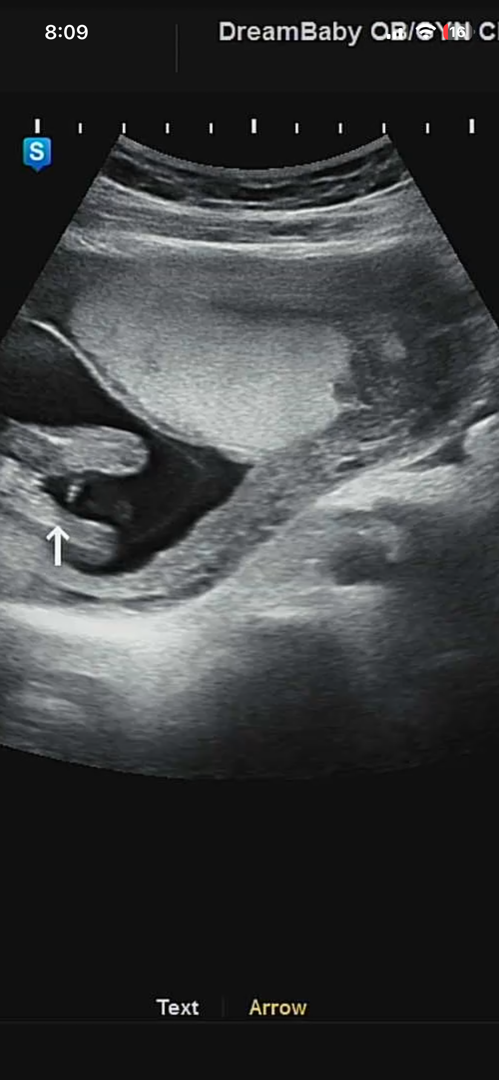

조심스레 딸..? 일 것 같아요..ㅎㅎ 니프티로 이미 아들확정받고 같은 각도로13주4일차 아들초음파 같이 첨부드려요

임신증상이나 태몽이나 주변에서 다 아들일것이다 확신했는데 어제 초음파보니 다리사이가 매끈하다네요?ㅎㅎㅎㅎ 애기가 너무 꼬물거려서 확실하지는 않은데 딸같대요! 여러분들이 보시기엔 어떤가용??ㅎㅎ